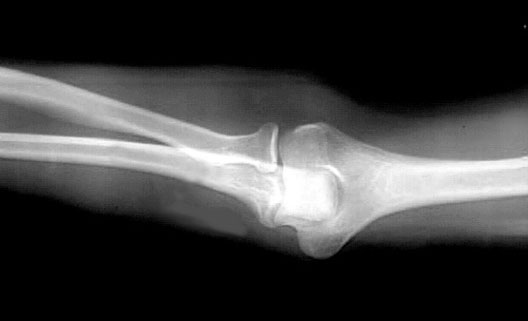

Elbow Extended

1. Radius

2. Radial Tuberosity

3. Lateral Epicondyle

4. Humerus

5. Ulna

6. Medial Epicondyle

7. Olecranon Process of Ulna